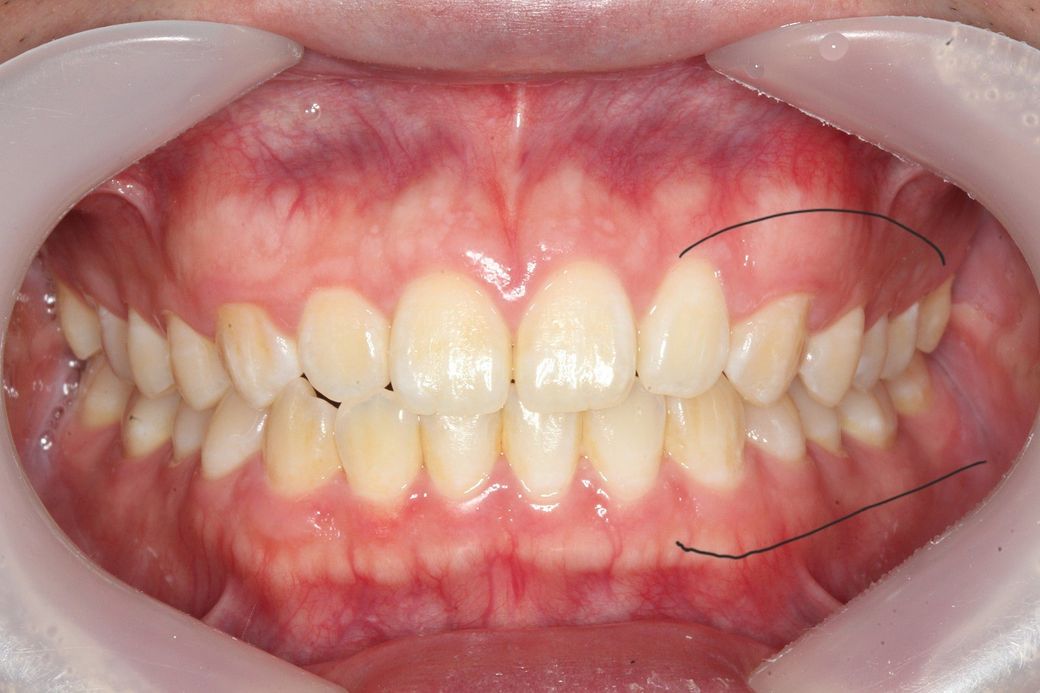

턱이 왼쪽으로 canting 되어있어도 어금니 교합이 맞을수 있나요?

턱이 왼쪽으로 비대칭이 약간 있는데 그래도 어금니 교합이 맞을수있나요?

주관적인 생각으로 약간 아랫뼈? 치아?들이 전체적으로 왼쪽으로 이동한 느낌인데 이러면 어금니 교합도 틀어지지않나요?

사진상 왼쪽어금니들은 윗아래 옆면 딱붙는 느낌이면

오른쪽은 옆면이 공간이 남는 느낌? 입니다

-현재 제 교합이 정상적인건지 궁금합니다

• 1번 째 사진

일전에도 문의주신 것으로 기억합니다. 현재 좌측으로 canting 되어 있으나 이는 사람에 따라서는 치료의 대상이 아닐 수도 있습니다. 모든 사람은 양쪽으로 모두 대칭인 수평인 경우는 거의 없으며 한쪽으로 canting되어 있는 경우가 많습니다. 이때 canting 범위에 따라 정상일 수도 있고 정상이 아닐 수도 있으나 이는 본인이 심미적으로 전혀 문제가 되지 않는다고 본다면 치료를 하지 않아도 됩니다.

현재 교합이 완전하다고 할 수는 없습니다. 따라서 교정적인 힘으로 치열을 바꿀 수는 있어 보여도 상당히 어려운 과정을 거쳐야할 것으로 보이며 교정 전 후가 크게 달라지지 않을 수 있어 보입니다. 발치 교정도 현재로서는 애매하고 비발치 교정에도 한계가 있어 보입니다. 즉 정상범주에서 특별히 많이 벗어나는 것이 아니라는 것입니다.

이상적인 교합이면 가장좋겠지만, 작성자님의 상태의 교합이 크게 문제가 되어 보이진 않습니다. 다만, 기능적으로 문제가 있다면 교정을 고려해보셔도 되지만, 기능상으로 크게 문제가 없다면 그냥 지내셔도 상관없을것같습니다.